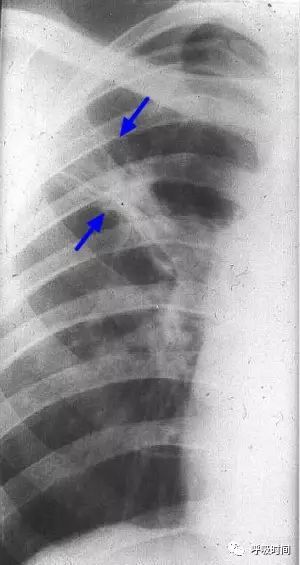

图片

图 10 肺纤维化病变影---陈旧性肺结核。右肺上叶可见条索状影(蓝箭头)